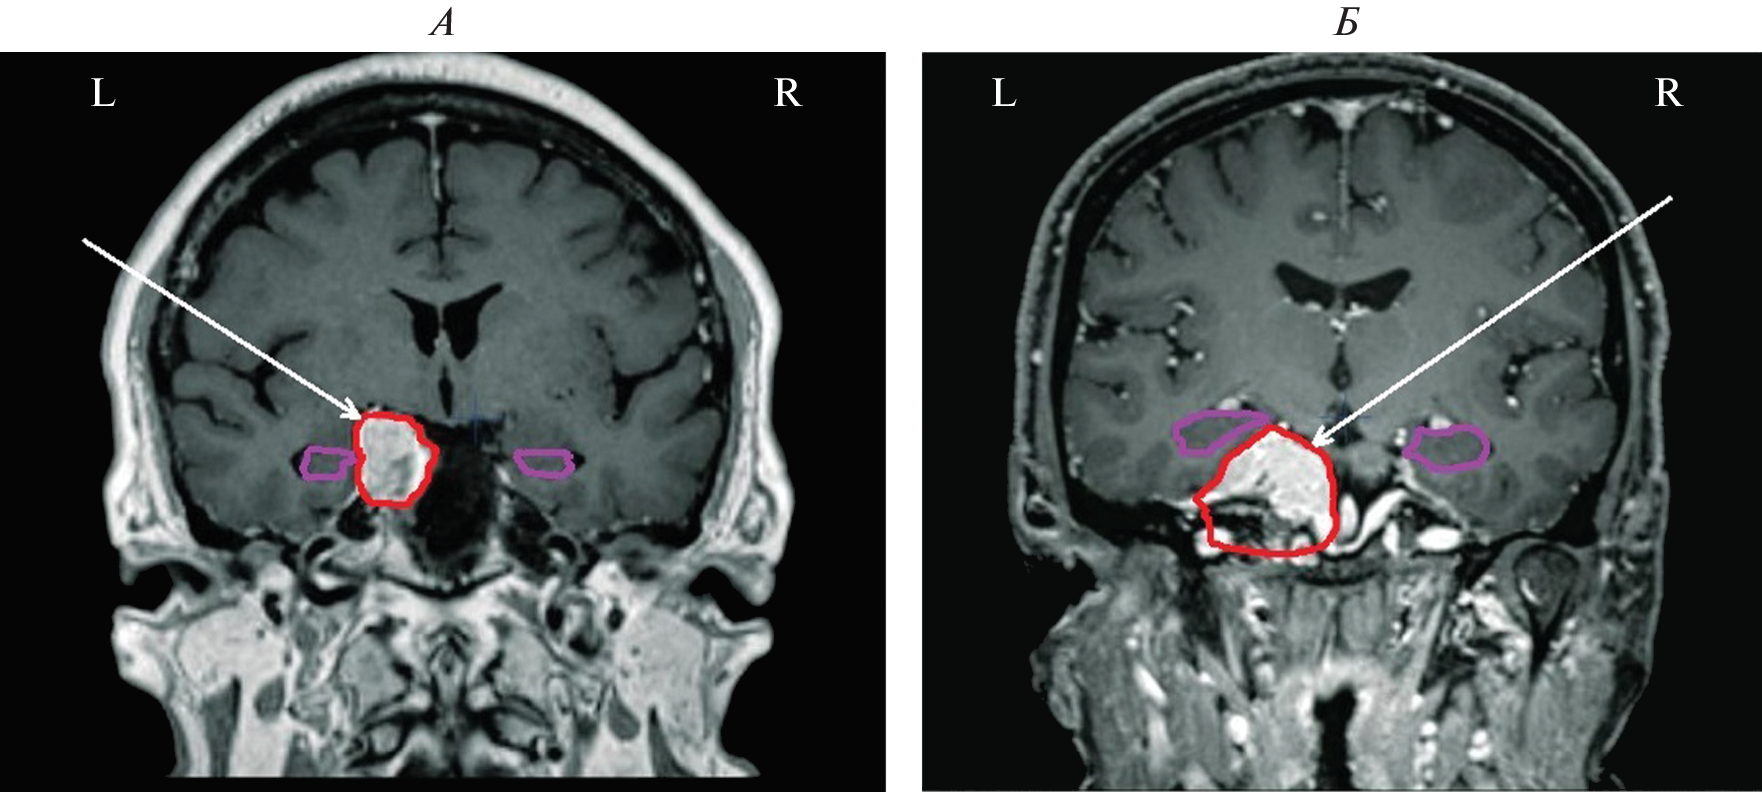

We studied the features of EEG and visual memory processes in 27 patients with a mediobasal regions extracerebral tumor of right and left hemispheres. According to neuroimaging (MRI) and morphometry, the degree of hippocampus involvement in pathological process was assessed. The predominant concentration of irritative-epileptiform signs in the affected hemisphere, as well as the presence of atypical alpha-rhythm episodes in the tumor projection zone, were classified as EEG markers of tumor compressive effect on the hippocampus. Signs of non-identical involvement of the right and left hippocampi in the pathological process were found in the form of a predominance of irritative signs in the left hemisphere throughout the group as a whole. Equivalent dipole sources (EDS) of atypical alpha rhythm are more confined to hippocampal structures than irritative EEG patterns. Neuropsychological testing of visual memory did not reveal significant disturbances in memory processes at this stage of the disease.

- Болдырева Г.Н. Атипичные формы церебральной альфа-активности при поражении регуляторных структур мозга человека // Физиология человека. 2018. Т. 44. № 3. С. 14. Boldyreva G.N. Atypical forms of cerebral alpha activity when human brain regulatory structures are damaged // Human Physiology. 2018. V. 44. № 3. P. 246.

- Болдырева Г.Н., Шарова Е.В., Коптелов Ю.М. и др. Исследование генеза патологических паттернов ЭЭГ при опухолевом и травматическом поражении мозга человека // Физиология человека. 2005. Т. 31. № 1. С. 24. Boldyreva G.N., Sharova E.V., Koptelov Yu.M. et al. Study of the genesis of pathological EEG patterns in tumor and traumatic lesions of the human brain // Human Physiology. 2005. V. 31. № 1. P. 18.

- Кулева А.Ю., Шарова Е.В., Болдырева Г.Н. и др. Особенности функциональной коннективности головного мозга в состоянии покоя у пациентов с латерализованным поражением медиобазальных отделов височной доли (данные фМРТ и ЭЭГ) // Журн. высш. нерв. деят. им. И.П. Павлова. 2022. Т. 72. № 2. С. 187. Kuleva A.Yu., Sharova E.V., Boldyreva G.N. et al. [Resting-state features of the brain functional connectivity in patients with lateralized temporal mediobasal lesions (fMRI and EEG data)] // Zh. Vyssh. Nerv. Deiat. Im. I.P. Pavlova. 2022. V. 72. № 2. P. 187.